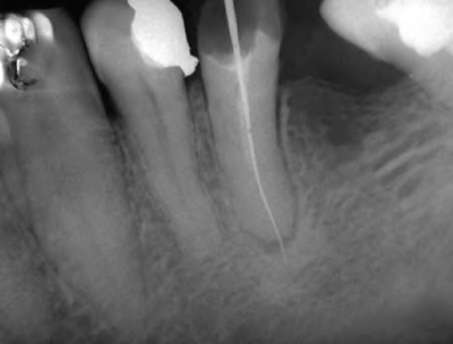

Учитывая, что клиническая картина хронического периодонтита может отсутствовать или быть незначительно выраженной для дифференциальной диагностики обязательно проведение рентгенографии. На рентгенограмме определяют деформацию периодонтальной щели с нарушением четких контуров компактной пластинки кости альвеолы. Многие случаи хронического апикального периодонтита связаны с некачественным эндодонтическим лечением (рис. 13-7).

image

Рис. 13-7. Хронический апикальный периодонтит зуба 35

Однако чаще на рентгенограмме у верхушки корня обычно определяют ограниченный очаг разрежения костной ткани округлой или овальной формы с четкими границами и остеосклерозом (рис. 13-8).